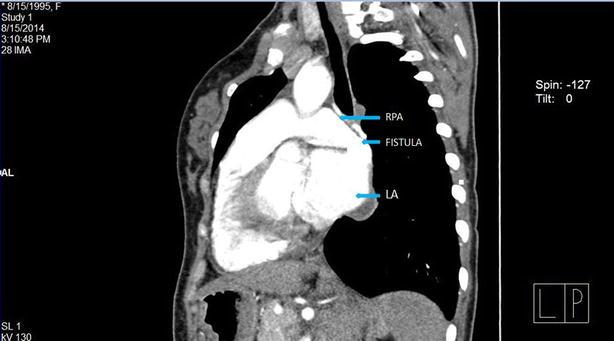

An uncommon variant of cyanotic congenital heart disease in a young adult female: a rare case of right pulmonary artery to left atrial fistula (PALAF).

Cyanotic congenital heart disease is not a rare entity, but fistula between the right pulmonary artery and the left atrium is an uncommon vascular anomaly. Although it is a real challenge to diagnose the case, detailed clinical evaluation and selective investigations are keys for diagnosis, and surgical intervention is still considered the best treatment option.

A 19 years old girl from the remote village of Nepal presented with the history of exercise intolerance associated with cyanosis and clubbing of the extremities. We diagnosed her as a case of right pulmonary artery to left atrial fistula, a rare variant of pulmonary arteriovenous malformation. She underwent successful surgical correction of the anomaly under cardiopulmonary bypass surgery.

Direct communication between the right pulmonary artery and the left atrium is a rare cyanotic congenital heart disease, which is diagnosed late and often associated with the atrial septal defect. The best treatment available is surgical correction.